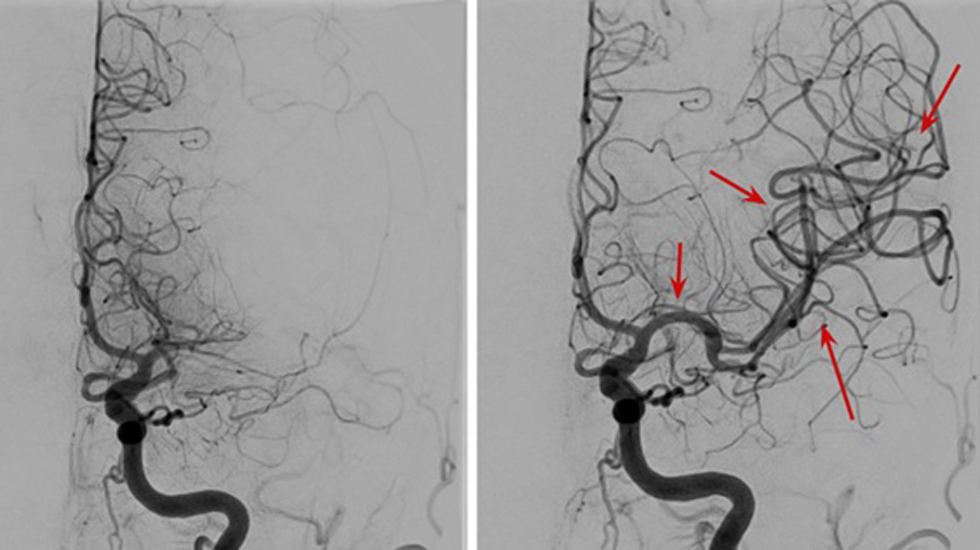

În data de 16 septembrie 2025, la Spitalul Clinic Județean de Urgență Bihor (SCJUBH), echipa de Radiologie și Neuroradiologie Intervențională, coordonată de Dr. Dan Mihoc, a realizat, în premieră pentru Oradea și regiune, tratamentul complet al două anevrisme cerebrale alăturate, la aceeași pacientă, într-o singură intervenție.

Procedura a fost efectuată prin implantarea unui dispozitiv modern numit Flow Diverter - un „stent cu plasă fină" care redirecționează fluxul sanguin și determină închiderea treptată a anevrismelor.

S-a efectuat un abord prin artera femurală dreaptă, a urmat apoi cateterizarea arterei carotide interne în porțiunea ei intracraniană și plasarea stentului exact la nivelul celor două anevrisme. Totul s-a desfășurat sub anestezie generală. După montarea stentului, toate materialele au fost extrase, iar locul puncției a fost închis cu un dispozitiv special - un dop de colagen resorbabil în maximum 3 luni.

Folosirea Flow Diverter-ului a redus timpul operator la doar o oră și jumătate și a scăzut semnificativ riscul de complicații. În absența acestui stent special, intervenția s-ar fi făcut tot endovascular, dar ar fi durat de 3-4 ori mai mult, ceea ce ar fi crescut riscul de complicații (precum AVC-ul ischemic iatrogen sau hemoragia intracraniană). Astfel, următoarea opțiune terapeutică ar fi fost plasarea de spirale de platină în cele două anevrisme - însă această tehnică prezintă riscul ca tratamentul să nu fie complet, rămânând porțiuni reziduale care, în timp, se pot mări și rupe.

Foto 4: Imagine angiografică (DSA) înainte și după o procedura de trombectomie mecanică prin care s-a desfundat practic o artera cerebrală principală care se înfundase cu un cheag de sânge (AVC ischemic).